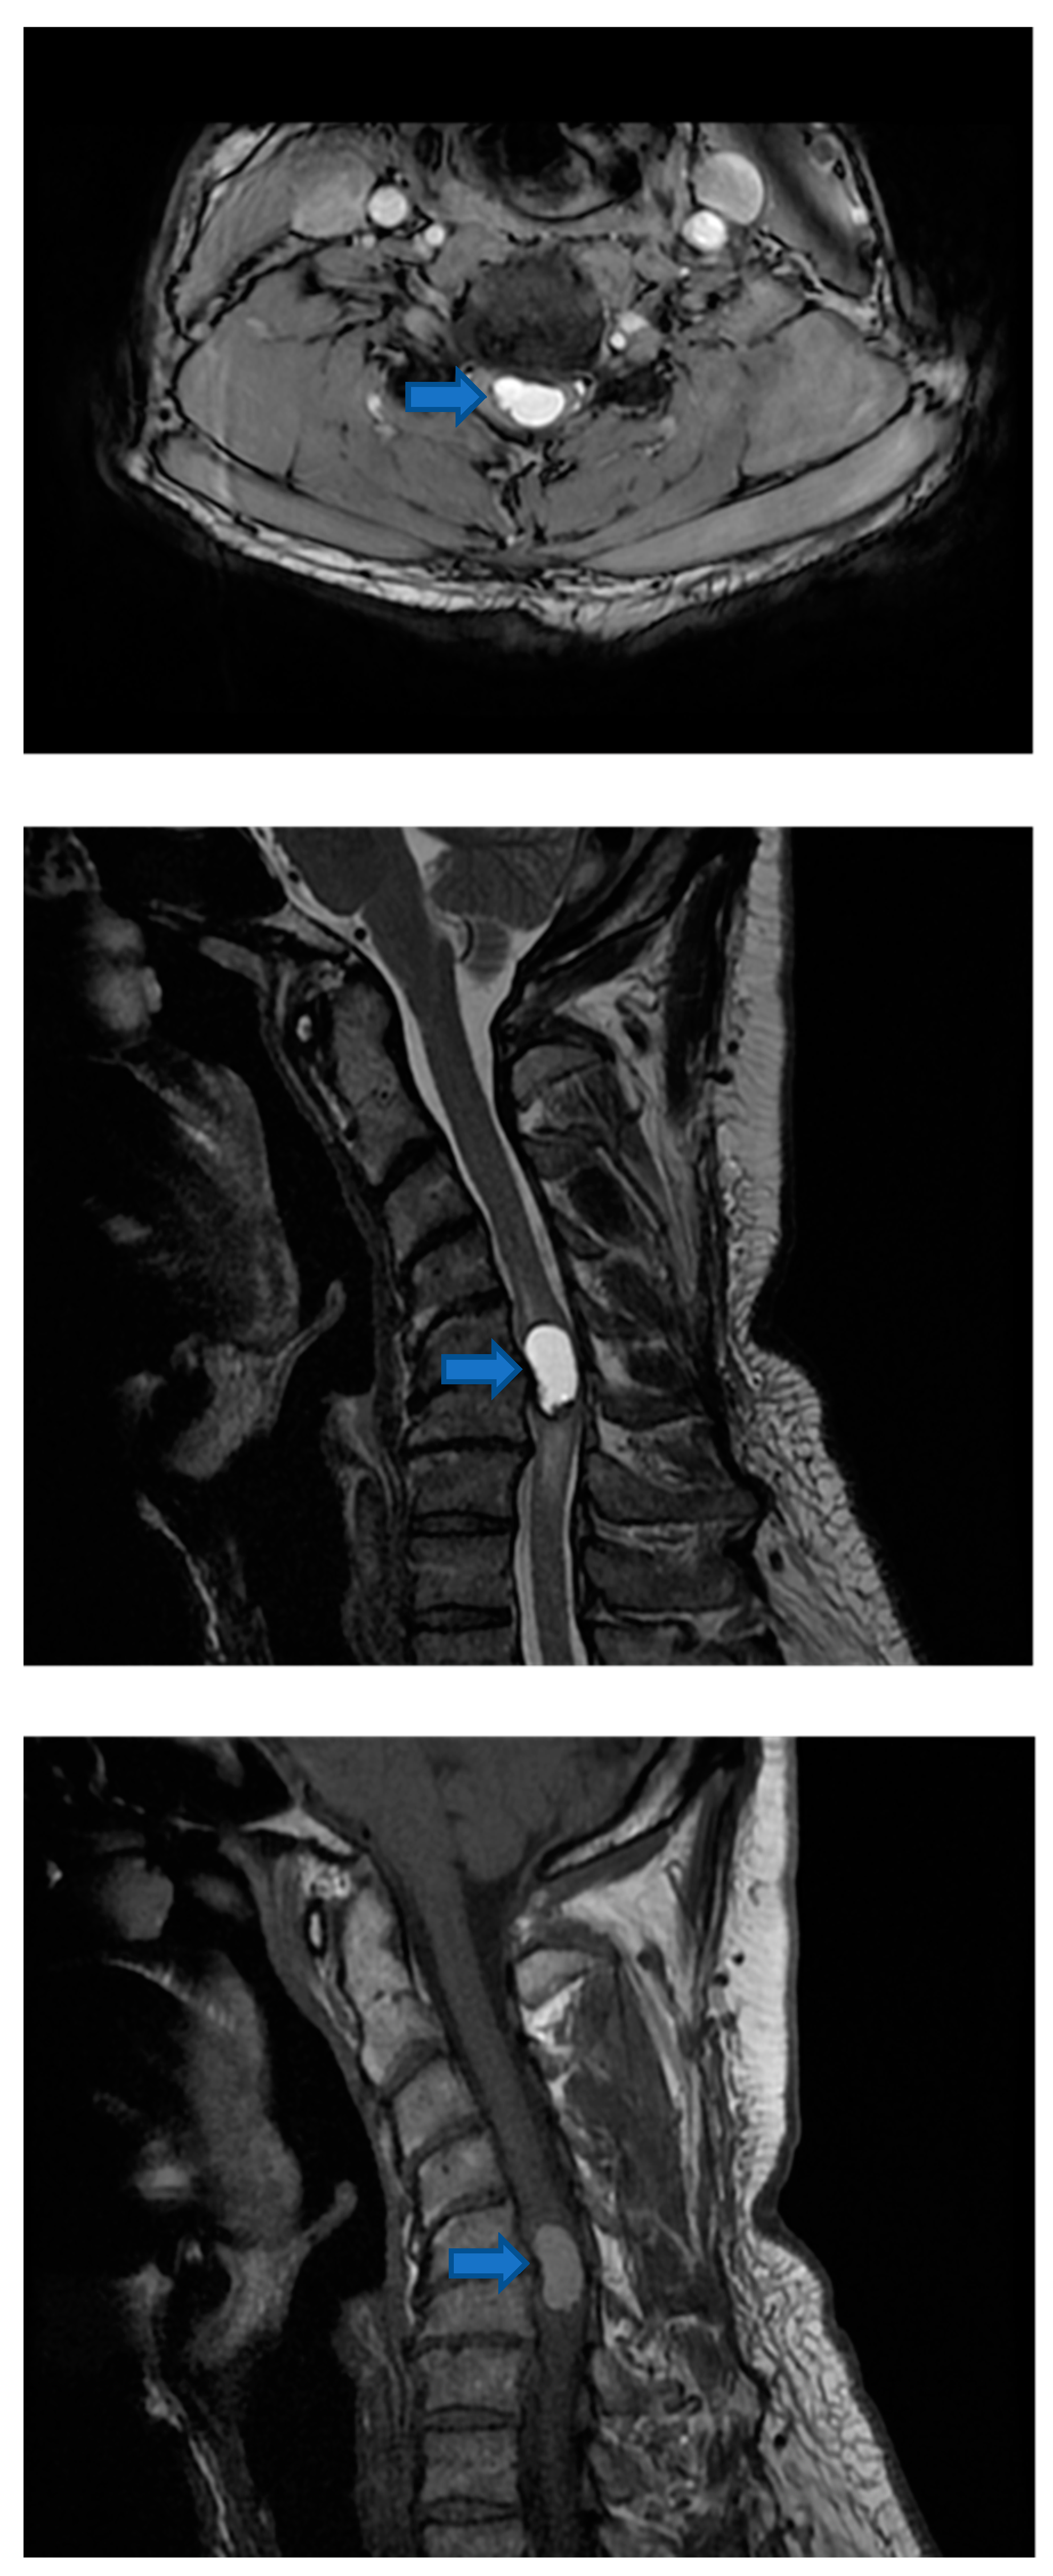

2.3. Post-Surgical Intervention Imaging